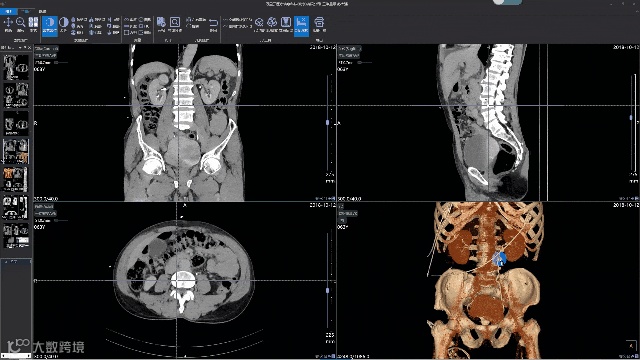

MPR/VR三维重建 ,AI专业诊断工作站支持VR和MPR三维重建功能,根据不同角度不同平面,多角度观察病变,使得病灶显示更加清晰。

集成业内优秀AI辅助诊断引擎 ,iPACS用户可一键式开启AI辅助诊断引擎,方便医生在线调阅申请服务,包括MR脑肿瘤、CT肺结节、CT脑出血、钼靶乳腺、心脏钙化积分等。